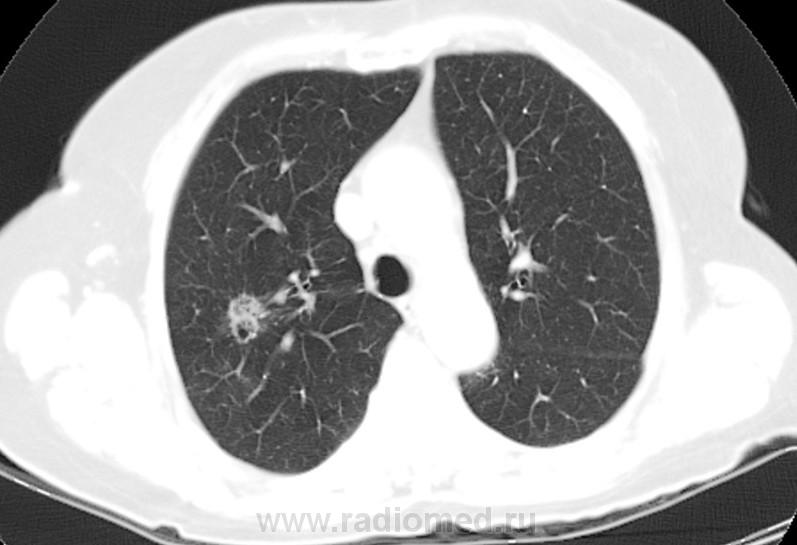

80 лет. Приехала к дочери из другого города. Последняя флюорография в 2010 г., на контроль не вызывали. Появился кашель. После флюорографии ( имеется плохой бумажный носитель) выполнили КТ ОГК. Со слов больной, в 1948 г. находилась в туберкулезном санатории. Подробностей не помнит. Специалисты по КТ заподозрили туберкулёму, каверну. Уж, больно тень нехорошая. Решил с Вами обсудить. Есть ли данные за рак? И каверна ли это? Рисунки представляю. Жизнь неумолимо диктует освоение КТ! Жду. С уважением Nik.

Впечатление туберкуломы с раком. Лимфангит (-оит, -иит), матовость нежная перифокально, очень может быть, что и очаговость.

Во-первых, такое впечатление, что образование состоит из нескольких узелков. От него идут в стороны линейные тени, скорее всего лимфангит, вокруг признак матового стекла. Распад есть, но существует ещё и полостная форма рака. Плюс возраст. Я за рак.

В S3 справа определяется участок уплотнения с четкими ровными контурами и уплотнением в центре (вероятнее всего туберкулема ).на границе S3 и S2определяется участок с разной денситометрческой плотностью,вероятнее всего сформированный из нескольких узлов(мультицентричный рост) имеющие вытянутую  ,округлую форму с бугристыми контурами ,с содержанием в структуре мелких бронхов,которое в  периферических отделах окруженно уплотнением по типу матового стекла(лимфостаз или перифокальное воспаление ),распорстраняющийся до костальной плевры,в ниже лежащем узле определяется участок распада с довольно плотной  капсулой ,в одном из сканов прослеживается бронх проникающий в образование ,выше и ниже участка определяются выраженные интерстициальные изменения. в средостенном окне, 2 скан-определяется участок деструкции ребра по ее  задней поверхности ,смешанного типа ,в участке прилежащем к мышцам определяется размытость контура с местами нарушением целостности замыкательной пластинки(исключить метастаз!!)у меня 3 диагноза :1)бар(локальная форма),2)карцинома и 3)множественные туберкулемы.в первую очередь исключить первые два,выяснить природу изменений в ребре

Больше в пользу рака. Неровные  лобулярные контуры, разная плотность (есть участки употнения по типу матового стекла. ззлокачественный характер кальцификации - эксцентрично, неравномерно, точечно). В образовании есть нарушение легочной архитектонники в виде расширениея мелких бронхов.  Вообщим, мне кажется (на 95% уверен) - это  периферический рак (ну или БАР)

Air Bronchogram sign Recent studies have showed that an air bronchogram is more commonly seen in malignant pulmonary nodules. It is most commonly seen in BAC (bronchoalveolar cell carcinoma) and adenocarcinoma. The case on the left shows an airbronchogram seen as a linear lucency (broad arrow) and as a more cystic lucency (small arrow) due to the fact that the bronchus is seen en face.

Solid and Ground-glass components Another result from screening studies is that nodules containing a ground-glass component are more likely to be malignant (5). Partly solid lesions with ground-glass components had a malignancy rate of 63%. Nonsolid - only ground-glass lesions had a malignancy rate of 18%. Only solid lesions had a malignancy rate of only 7%.

На 12 представленной картинке признаки диффузного интерстициального процесса в легких -  утолщение  легочного интерстиция с нарушеним легочной архитектоники (фиброз), с наличием нерезко тракционно расширенных бронхов с обеих сторон. Диффузное неоднородные участки снижения по типу "матового стекла" - КТ-картина больше в пользу неспецифической интерстициальнйо пневмонии (NSIP). Во всяком случае так смотрится на первый взгляд - конечно тут решает анамнез , клиника и динамика изменений. (а иногда и биопсия). А при изменениях по типу NSIP - диф. ряд большой.

Кстати на картинке озаглавленной "1. мозговой штурм" выше - есть очеь очень некрасиввый очаг в 6-ке слева (по типу матового стекла), расположенный периваскулярно. Очень подозрительный на мтс.